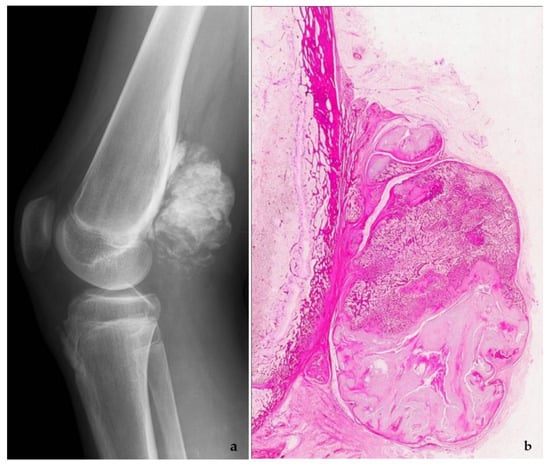

5. Low-Grade Osteosarcoma

Low-grade osteosarcomas are rare and are subdivided in parosteal and low-grade central osteosarcoma. In both tumors, the diagnosis is often impossible in the absence of imaging features, because they often look deceptively bland. Parosteal osteosarcoma represents 4–5% of all osteosarcomas and is the most frequent surface osteosarcoma. It typically develops on the posterior surface of the distal femur of young adults, mainly in the third decade. The humerus can also be rarely involved. On imaging, a heavily mineralized mass attached to the cortex is seen (Figure 11). Histologically, fascicles of non-atypical spindle cells admixed with parallel bone trabecula are typical (Figure 11). In half of the cases, cartilage islands can be seen, and about half of the tumors transgress the cortex and invade the medullary cavity. Fifteen to 43% dedifferentiate into a high grade (osteo)sarcoma []. Low grade central osteosarcoma only accounts for 1–2% of osteosarcomas and is mainly seen in the metaphysis of long bones, tibia and femur being most affected. This tumor rarely involves jaw bones, axial and small tubular bones. Half of the cases occur in the second to third decade. On imaging, a large lytic to mineralized mass is seen, often associated with focal cortical disruption, which can be hard to see (Figure 12). On histology, the tumor consists of a fascicular and moderately cellular fibroblastic proliferation, with minimal or no atypia. The neoplastic bone can present as curved bone trabeculae, mimicking fibrous dysplasia, or as longitudinal seams of bone, as seen in parosteal osteosarcoma (Figure 12). Bone formation can even be absent, resulting in a picture that resembles desmoplastic fibroma or low-grade fibrosarcoma. Very rarely dedifferentiation can occur resulting in a classical high-grade osteosarcoma-like picture []. Both tumors harbor long marker or ring chromosomes with amplified 12q13-15 regions, including the MDM2 and CDK4 genes [,]. In a high proportion of cases, immunohistochemical MDM2 and/or CDK4 expression can be found as well. In this respect, search for MDM2 amplification/expression can be very useful to distinguish these low-grade sarcomas from their—often benign—mimics (Figure 11 and Figure 12) []. The prognosis of both neoplasms is excellent, with 5-year survival rates of 90% upon complete resection. Chemotherapy is only administered in cases of dedifferentiation, when the prognosis is that of a conventional osteosarcoma. Interestingly, when low-grade central or parosteal osteosarcoma dedifferentiate into a high-grade sarcoma, they retain their MDM2/CDK4 amplification and overexpression. In addition, the finding of MDM2 and/or CDK4 amplification/overexpression in a high-grade osteosarcoma indicates progression/dedifferentiation from a low-grade osteosarcoma and practically excludes a primary conventional high-grade osteosarcoma [].

Figure 11.

Parosteal osteosarcoma, typically presenting as a mineralized mass at the back of the distal femur, X-ray (a), and whole mount section (b). At high power, the tumor consists of parallel bone trabeculae and a typical spindle cell proliferation (c). MDM2 expression is present as well (d).